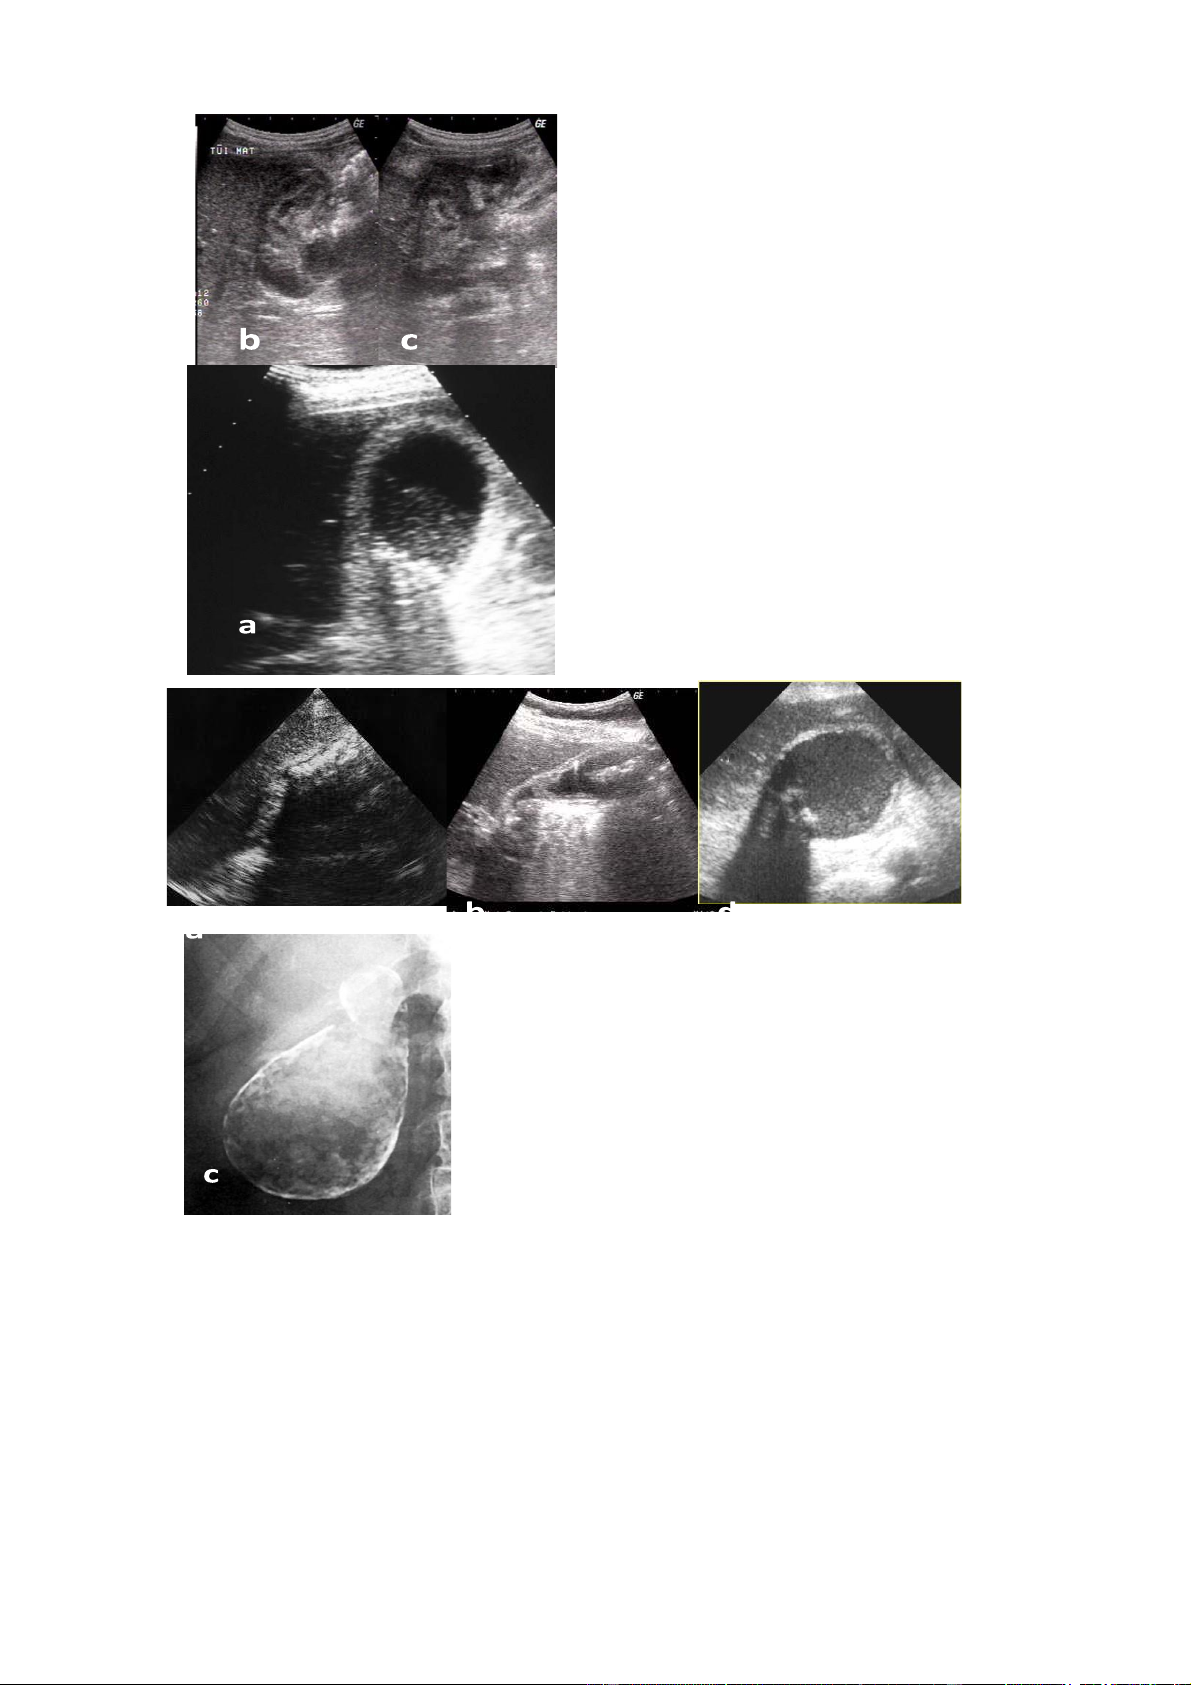

bHình. 6,1.3. sỏi túi mật a. Nhiều sỏi túi mật b.

sỏi phểu túi mật + viêm túi mật cấp c.

sỏi kẹt phểu và túi mật chất đầy bùn mât

Hình 6.1.4 . Viêm túi mật cấp

a.Viêm túi mật cấp thể nhẹ: thành

túi mật dày, dịch quanh túi mật, sỏi túi mật.

b, c. Viêm túi mật cấp hoại tử:

thành túi mật dày, gián đoạn, áp xe quanh túi mật

Hình 6.1.5 . Viêm túi mật mạn

a. Viêm teo túi mật: túi mật teo nhỏ, thành

dày, chất đầy sỏi, không còn dịch mật

b. Viêm túi mật mạn: túi mật vẫn còn dịch

mật, có sỏi, thành dày tăng âm và có

lắng đọng cholesterole trong thành.

c. Thành túi mật vôi hoá: hình trên phim

chụp khu trú vùng gan mật

d. Thành túi mật vôi hoá: hình siêu âm